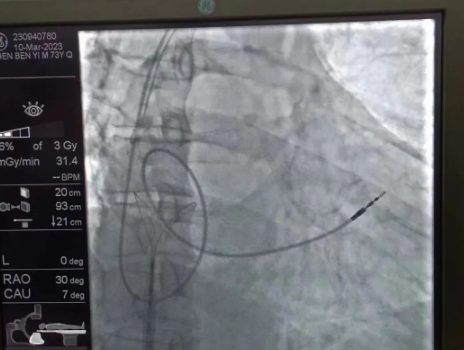

“成功拔除心臟起搏電極。”心臟DSA手術室外,觀摩手術的醫(yī)生中爆發(fā)出一陣熱烈的掌聲。3月10日,西安國際醫(yī)學中心醫(yī)院心臟病醫(yī)院副院長李偉杰教授為一名老年男性患者成功拔除了斷裂的心臟起搏電極,并為患者植入新的起搏電極。

術中,孫書紅醫(yī)師首先切開起搏器囊袋,游離出起搏器脈沖發(fā)生器,發(fā)現(xiàn)起搏電極完全斷裂,連接于起搏脈沖發(fā)生器,殘端約10cm;考慮患者為起搏依賴患者,需再次植入新的起搏電極導線,穿刺了腋靜脈,放置導絲;同時,李偉杰教授穿刺了左、右股靜脈,于右股靜脈置入了”抓捕器”,左股靜脈備用臨時起搏通路,以防術中出現(xiàn)心跳驟停。為了準確抓捕到心房內(nèi)的在逃起搏電極,李偉杰教授將導管室的X光機球管調整成了冠脈模式,這就意味著在抓捕過程中,醫(yī)生要比平時的手術“吃”更多射線……

在透視模式下,抓捕全憑醫(yī)生的經(jīng)驗與手感,一次次嘗試,一次次失敗,在場外觀摩手術的醫(yī)生同樣為李偉杰教授捏了一把汗,“找到了!”電子屏里抓捕器向在逃起搏電極“發(fā)起進攻”,一把逮住并順利拔出一根長達58cm的起搏電極。